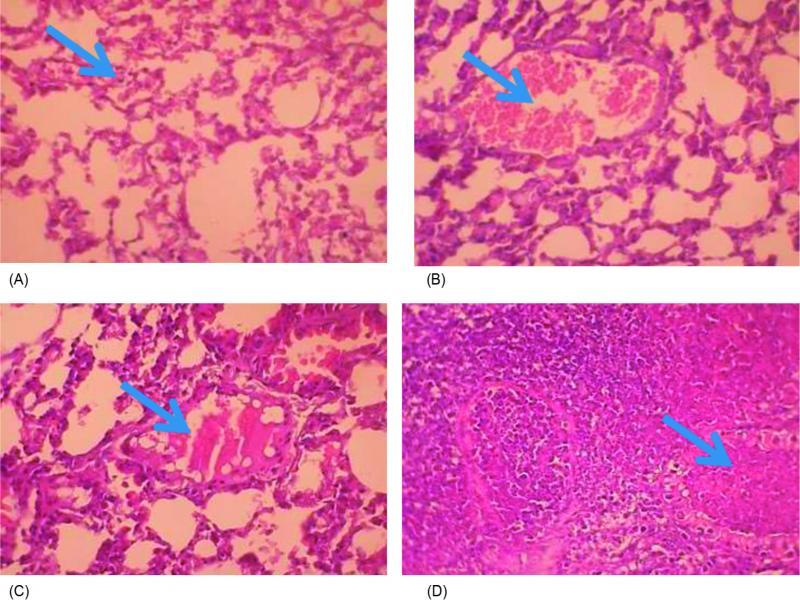

The histopathological examination of lung tissue sections obtained from CIP-treated mice group showed obvious features of acute bronchopneumonia almost the same as those in the untreated control with marked congestion, oedema, inflammatory infiltration, necrosis with accumulation of necro-inflammatory exudate within the lumen of bronchioles (Fig. 3). The lungs of ZAB-treated mice group revealed very mild congestion and inflammation with scarce inflammatory cells in the interstitial spaces. The mice group treated with MOX and LEV displayed moderate interstitial inflammation, moderate congestion and oedema (Fig. 3). Figure 4 demonstrates a patent alveolus dissected from ZAB-treated mice group, showing clear alveolar spaces and normal vessels and bronchioles lined by a layer of pneumocytes. The degree of congestion, inflammation, oedema and necrosis was scored using a scoring system adapted from Dubin and Kolls (2007) and summarized in Table V. Mice groups infected with MRSA clinical isolate S19 and treated with ZAB at an adjusted dose of 20 mg/kg of body weight/day, displayed best scores with least detected congestion, inflammation, oedema and necrosis followed by MOX, then LEV and finally CIP, all administrated at same dose regimen.

Lung tissue sections dissected from mice infected with MRSA clinical isolate and treated with (A) zabofloxacin showing very mild congestion (arrow) and inflammation with scarce inflammatory cells in the interstitial spaces; (B) moxifloxacin showing moderate congestion with ectatic vessels (arrow) and moderate interstitial inflammation; (C) levofloxacin showing moderate inflammation, congestion and oedema, with a dilated lymphatic vessel (arrow); and (D) ciprofloxacin showing bronchopneumonic changes with marked congestion, oedema, inflammatory infiltration and necrosis, with accumulation of necro-inflammatory exudate within the lumen of bronchioles (arrow) (H&E x400).

The in vivo studies demonstrated that ZAB possessed the most potent protective effect against systemic infection caused by a MRSA strain isolated from bronchoalveolar lavage (Table IV), similar findings being reported by Kwon et al. (2006) and Park et al. (2006). The histopathological examination of lung specimens of mice infected with MRSA isolate and treated with ZAB displayed least congestion, inflammation, oedema and necrosis (Table V; Fig. 3); the examined alveoli displayed clear alveolar spaces and normal vessels (Fig. 4).